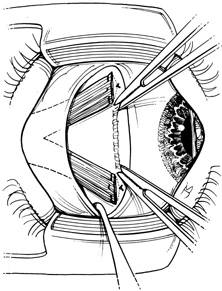

Step 2. A Stevens hook is brought from beneath the muscle to perforate it at its midpoint. Then, the hook is used to split the muscle into equal halves for a distance of 15 mm posterior to its insertion (Fig. 2). Blunt Westcott scissors may be used to complete the ends of the split, particularly at the muscle insertion (Fig. 3).

Fig. 2. A Stevens hook is brought from beneath the muscle to perforate it at its midpoint. Then, the hook is used to split the muscle into equal halves for a distance of 15 mm posterior to its insertion.

Fig. 3. Blunt Westcott scissors may be used to complete the ends of the split, particularly at the muscle insertion.